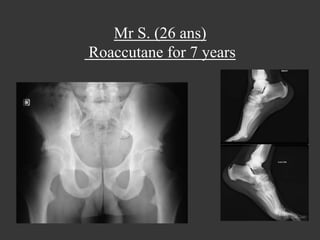

Mr S. (26 ans)

Roaccutane for 7 years

Roaccutane (isotrétinoïne):

8 months in 2007 and 4 months in

2010 !!!

Isotrétinoïne and bones

•  Sacroiliitis : seldom

*E. Eksioglu et al., Sacroiliitis and polyneuropathy during isotrtinoin treatment 2007

*Elias et al.,Acne fulminans and bilateral seronegative sacroiliitis triggered by isotretinoin 1991

*Bachmeyer et al., Isotretinoin induced bilateral sacroiliitis 2003

•  Diffuse Idiopathic Skeletal Hyperostosis like

Hyperostosis and calcification of tendons and ligaments

Bone bridges along the anterior longitudinal ligament (6

vertebrae at least)

*J. DiGiovanna et al., Isotretinoin effects on bone